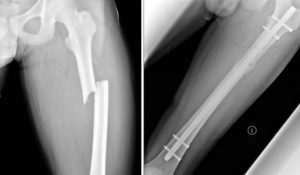

Ниже представлены изображения различных переломов femur в наиболее типичных местах.

Такой перелом хорошо диагностируется с помощью рентгена

Операция заключается в репозиции отломков и фиксации их металлическим стержнем или пластиной. Двойной перелом со смещением — абсолютное показание к оперативному вмешательству. После фиксации отломков необходимо наложение гипсовой повязки.

- Операция на бедренной кости. Она заключается в фиксации кости при помощи специального штифта.

Также фиксацию сломанной кости производят специальными пластинами.

Для этого применяют остеосинтез, который заключается в закреплении костных отломков металлическими штифтами, винтами, пластинами. При оскольчатых травмах левого и правого бедра используют аппарат внешней фиксации типа Илизарова. Крепления для остеосинтеза обычно убирают через год после операции.